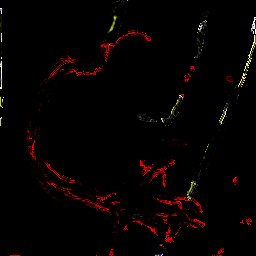

Using the approach discussed in section 3.2 we automatically generated annotations for 3000 randomly selected frames from sequences different than those with manual ground truth. In order to highlight the difference between the manual and automatic segmentation we present both in figure 4. The ground truth mask includes three labels i.e. background (black), vessel tree (red), and catheter (yellow). Black top-hat based segmentation mask contains significant noise, boundary irregularities and large parts of vessels as well as catheter are missing. The masks filtered with connected components seem to reduce the amount of noise but also further remove some small valid segments. This is crucial when comparing quantitative results of this simple segmentation method with and without connected component filter in Section 4.2.

3000 pairs of frames with their optical flow from the automatically generated dataset were used to train the binary U-Net and the Siamese U-Net models presented in Sections 3.1 and 3.3. As illustrated in Figure 4(f) the Siamese U-Net is more accurate than the baseline U-Net. U-Net fine-tuned with manually annotated and augmented data provides masks with less noise and smooth object boundaries, although the same segments are successfully extracted in both, unsupervised Siamese U-Net and the fine-tuned one.